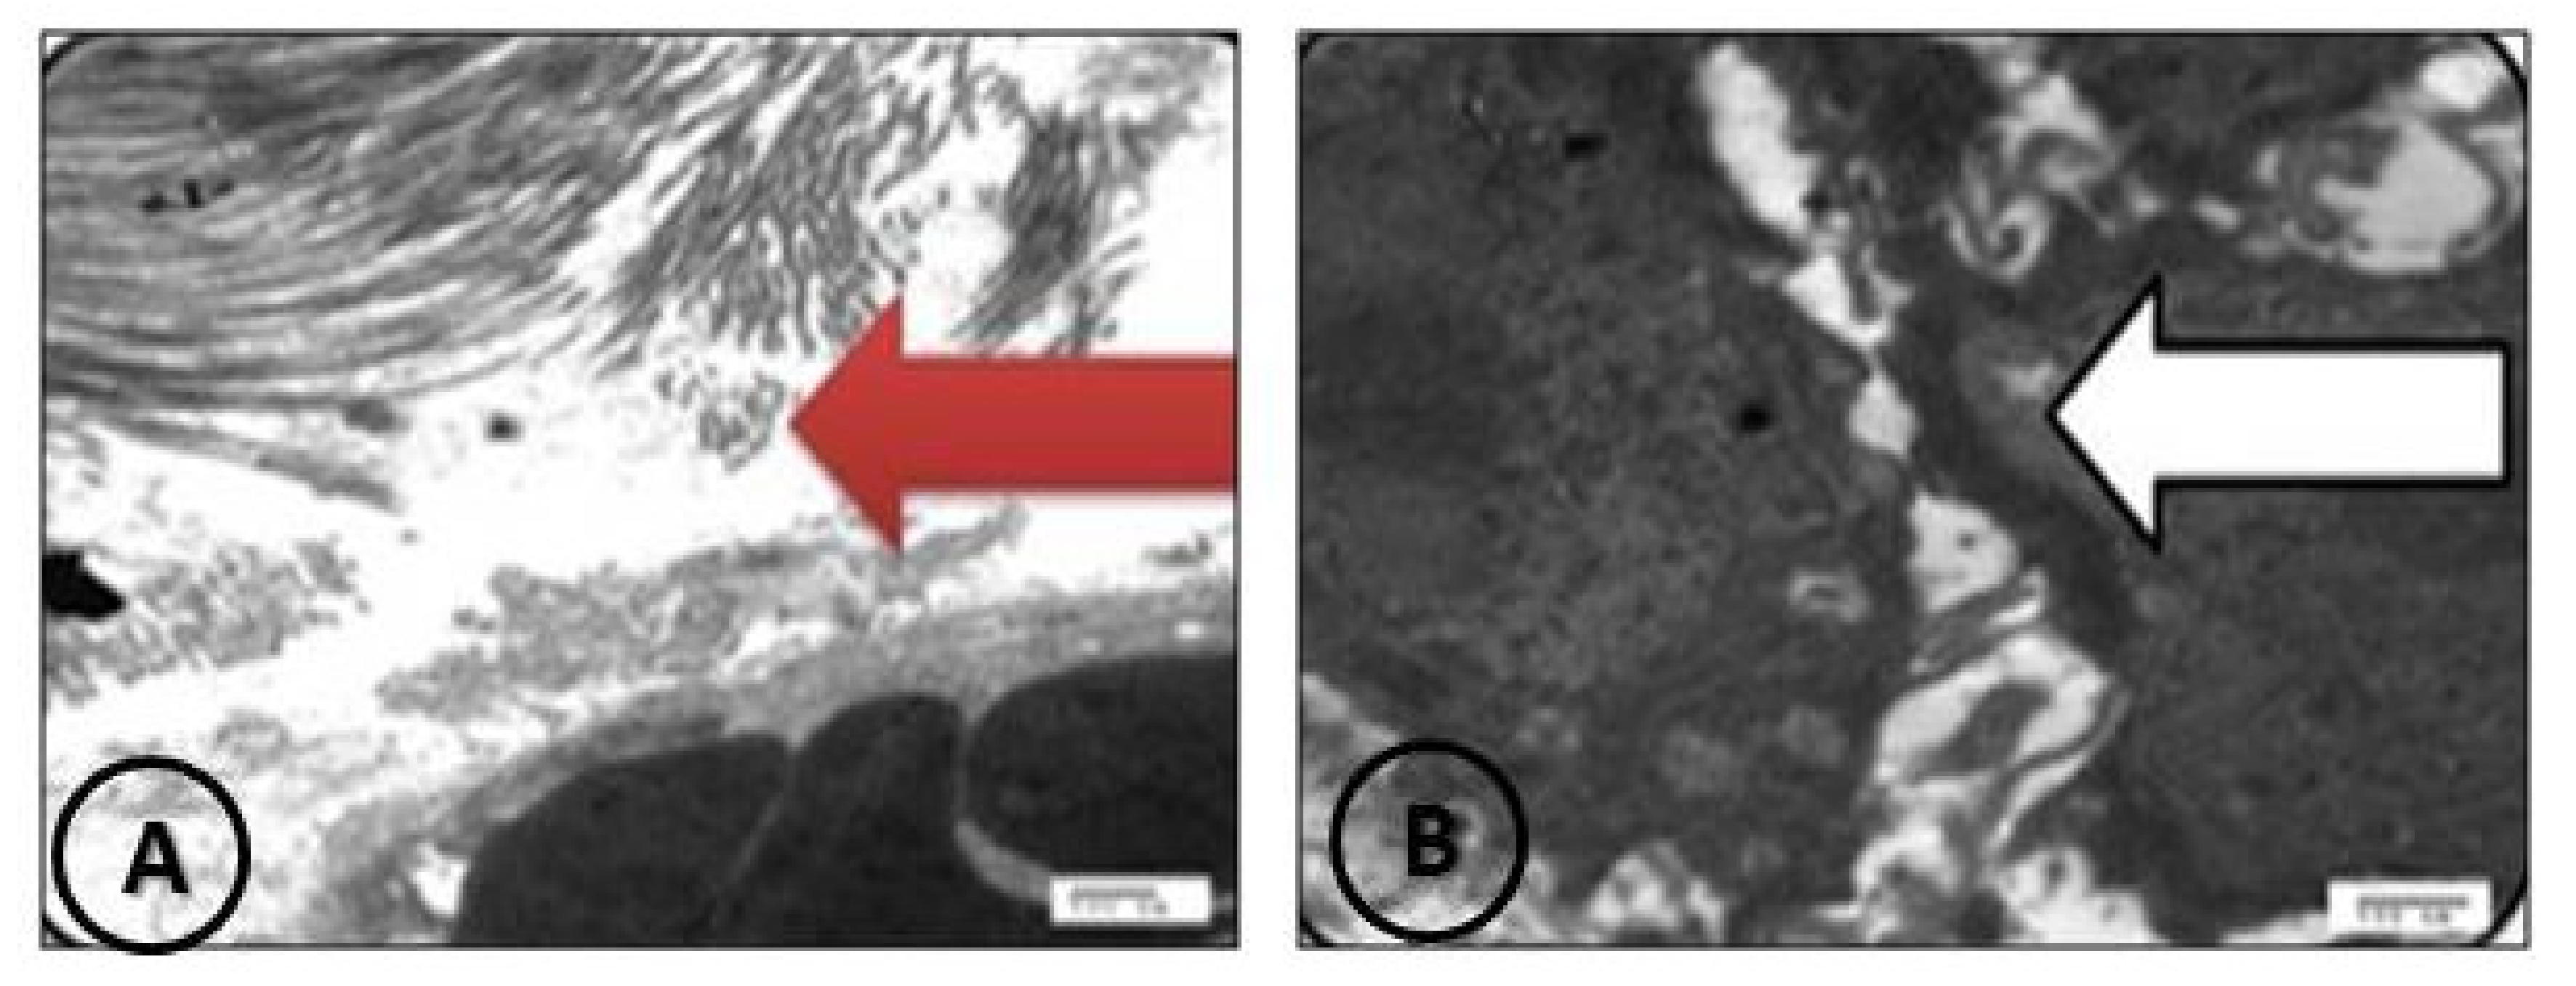

3.2.8. TEM Examination